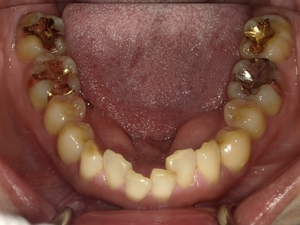

すきっぱ(空隙歯列)CASE4 2023.06.06 40代女性非抜歯BEFORE→AFTER〇ご相談内容:歯と歯の間があいている、下の歯のがたつき〇矯正の種類:マウスピース型矯正「インビザラインGO」〇治療期間:17週間〇治療費用:44万円(税込) < すきっぱ(空隙歯列)CASE5すきっ歯(空隙歯列弓)CASE3 > ブログ記事一覧をみる